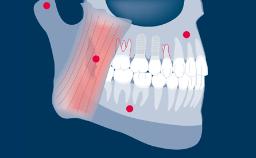

As próteses provisórias desempenham um papel importante na substituição de dentes perdidos durante a terapia com implantes, até o ponto em que os implantes estão prontos para serem restaurados. A terapia com implantes geralmente envolve vários estágios clínicos e laboratoriais, e as próteses provisórias buscam garantir que o paciente esteja confortável em um nível estético e funcional durante toda a duração do tratamento. As próteses provisórias também têm importantes funções diagnósticas e podem ser um fator-chave para alcançar a satisfação do paciente com o resultado definitivo do tratamento. Existem várias opções de próteses provisórias, fixas e removíveis.